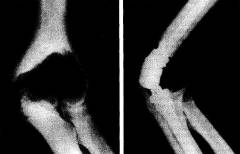

Перелом костей локтя — распространенная травма, возникающая при механическом воздействии. Перелом может произойти при падениях, ударах или компрессии.

При переломе возникают боли, отек, подкожные кровотечения и ограничение движений. В некоторых случаях перелом может быть открытым.

Перелом может затрагивать один или несколько участков костей, формирующих локтевой сустав, с образованием острых осколков, повреждающих соседние структуры.

Диагностика перелома основывается на лучевых методах (рентгенография, КТ), которые помогают выявить костные дефекты.

Методы диагностики перелома костей локтя:

- Анамнез. Установление признаков перелома и причины болей.

- Внешний осмотр. Выявление гематом и отечности.

- Рентгенография и компьютерная томография. Устанавливают локализацию и вид перелома.

В зависимости от характера перелома врач выбирает тактику лечения.